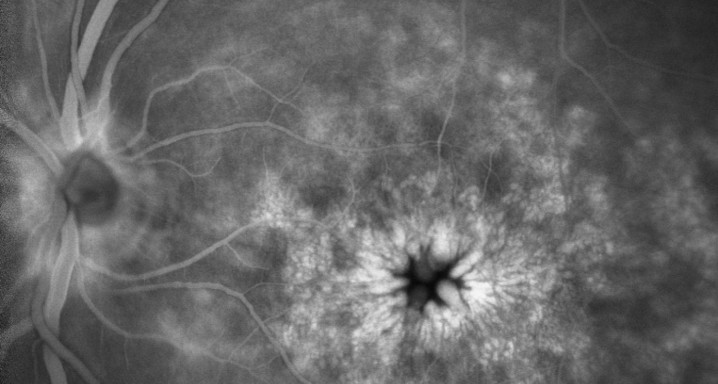

Postsurgical cystoid macular edema 26/03/2013

Cystoid macular edema (CME) is a primary cause of postoperative reduced vision. It may occur even when the intraoperative course is successful for operations such as cataract and vitreoretinal surgery. Its incidence following modern cataract surgery is 0.1%-2.35%. This risk is increased if there are certain preexisting systemic or ocular conditions and when there are intraoperative complications. The etiology of CME is not completely understood. Prolapsed or incarcerated vitreous and postoperative inflammatory processes have been proposed as causative agents. Pseudophakic CME is characterized by poor postoperative visual acuity. Fluorescein angiography is indispensable in the workup of CME, showing the classical perifoveal petaloid staining pattern and late leakage of the optic disk. Optical coherence tomography is a useful diagnostic tool, which displays cystic spaces in the outer nuclear layer. The most important differential diagnoses include age-related macular degeneration and other causes of CME such as diabetic macular edema. Most cases of pseudophakic CME resolve spontaneously. The value of prophylactic treatment is doubtful. First-line treatment of postsurgical CME should include topical nonsteroidal anti-inflammatory drugs and corticosteroids. Oral carbonic anhydrase inhibitors can be considered complementary. In cases of resistant CME, periocular or intraocular corticosteroids present an option. Antiangiogenic agents, though experimental, should be considered for nonresponsive persistent CME. Surgical options should be reserved for special indications.